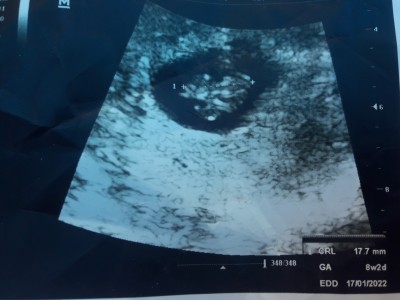

Yaşadığım bazı sebeplerden dolayı bebeğimi aldircaktim ama vazgeçtim doğurmaya karar verdim tek başıma bakıp buyutucem herneyse bugün kontrole gittim 8 haftalık cinsiyeti belli olur mu tahmin sadece bilenler yardımcı olabilir mı:)

Gebelik haftası 8